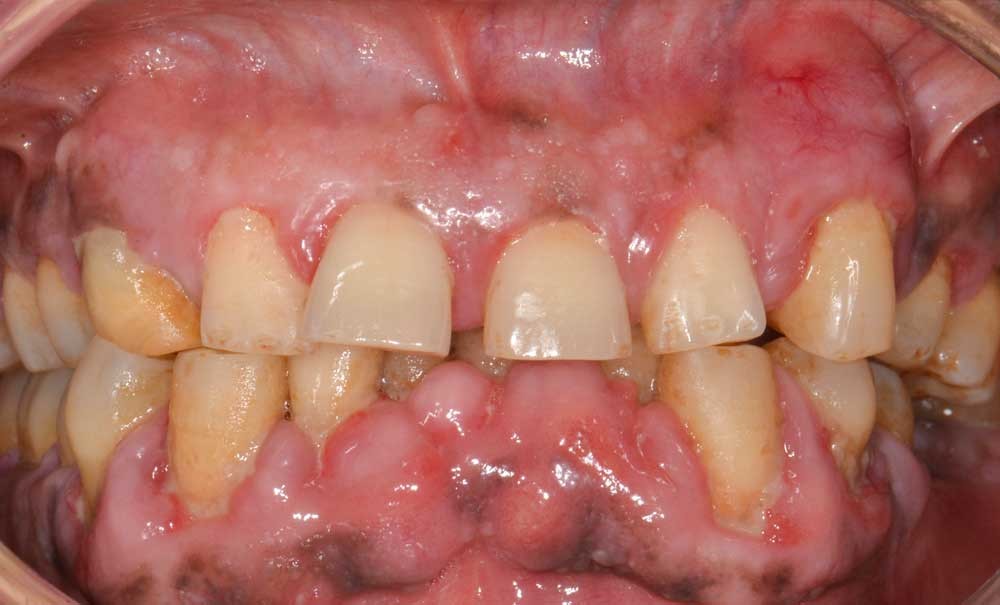

Déterminer si une dent est compromise revient à établir son pronostic dès le début du traitement, en tenant compte des paramètres cliniques, radiographiques, des facteurs propres au patient et du plan de traitement global. Le pronostic reste évolutif et doit être réévalué tout au long du traitement (fig. 1).

Selon les principales classifications pronostiques proposées dans la littérature (2-5), une dent est considérée comme « compromise » sur le plan parodontal lorsque son pronostic est jugé « discutable » ou « sans espoir ». Cela correspond à la présence d’un ou plusieurs des critères suivants :

- poche parodontale profonde (≥ 6 mm) ;

- perte osseuse sévère (> 50 % selon les auteurs, dont Cárcamo-España 2022 [6]) ;

- mobilité de classe II (déplacement horizontal ≥ 1 mm) ou III (mobilité axiale) (classification de Miller [7]) ;

- atteinte de furcation de classe II (sondage > 3 mm sans passer de part en part) ou III (sondage de part en part) pour les dents pluriradiculées (classification de Hamp [8]).

Parmi ces critères, seule la mobilité axiale, liée à une alvéolyse terminale due à la parodontite (et non à un élargissement desmodontal par trauma occlusal) constitue une indication d’avulsion. Les autres facteurs, pris individuellement, peuvent être améliorés au cours du traitement. Examinons-les un par un.